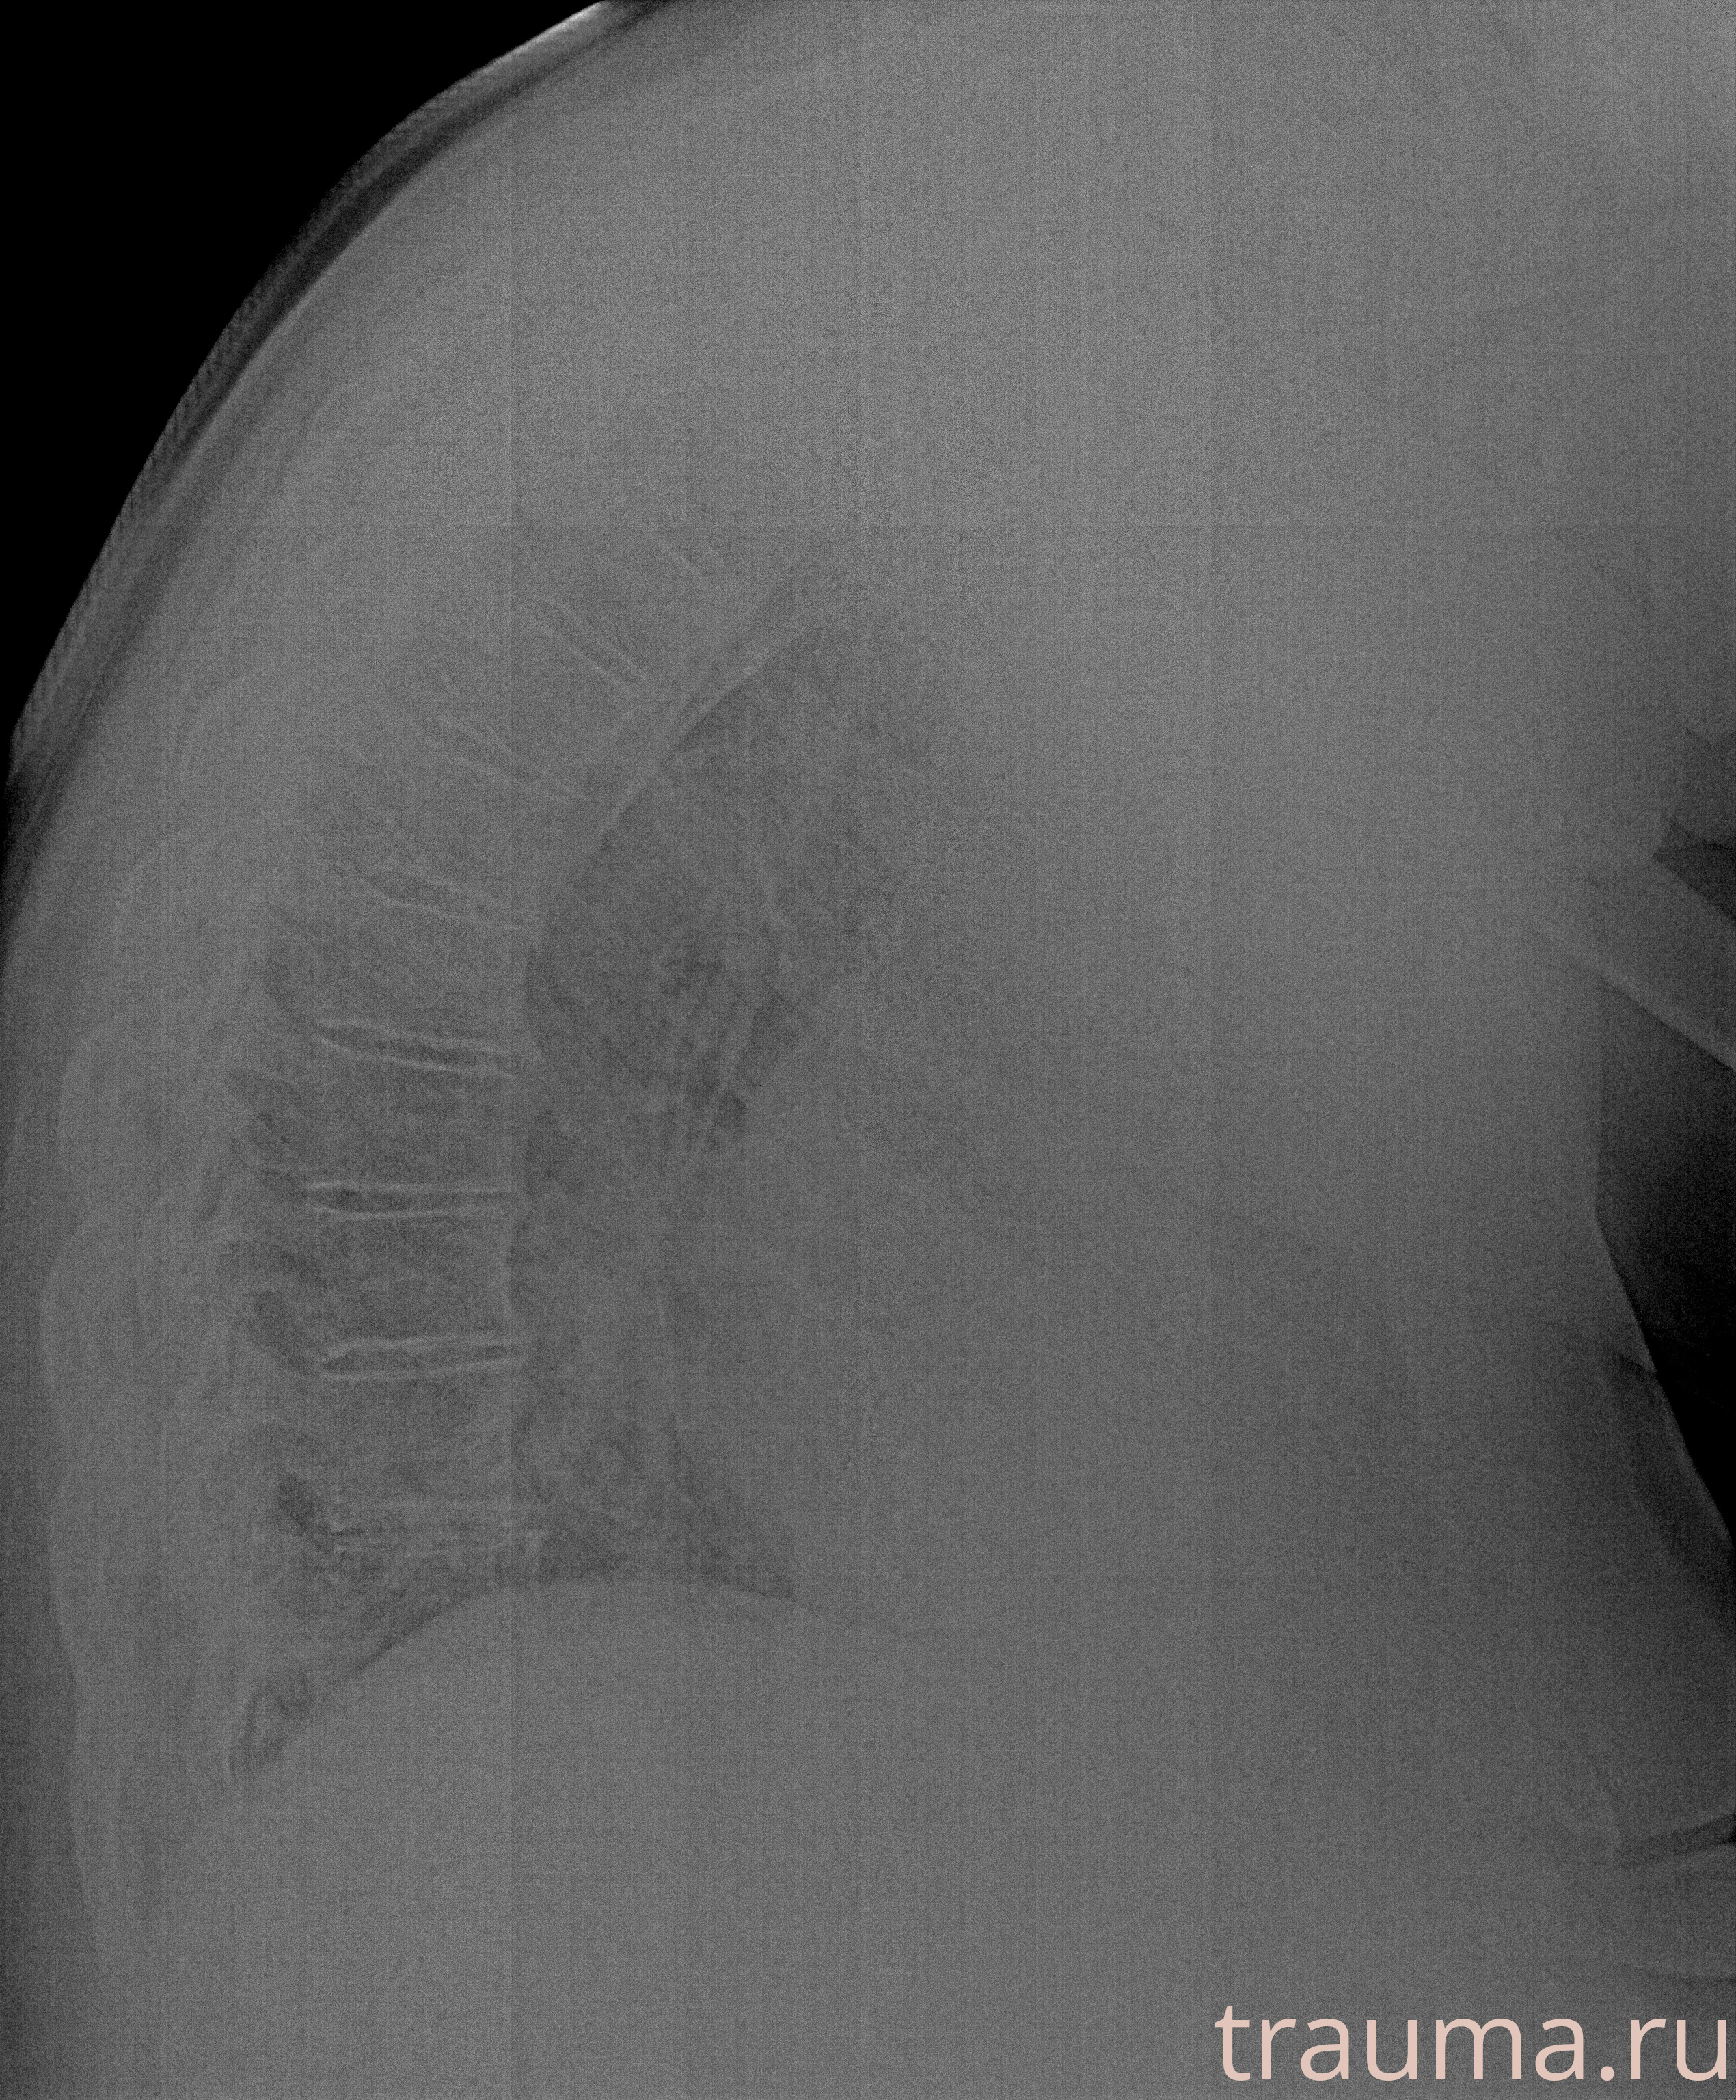

Рентгенограммы

Рентген на дому: по вашему адресу приезжает врач-рентгенолог, травматолог-ортопед с мобильным рентгеновским аппаратом, проводит диагностику травмы или заболевания, делает необходимые рентгенограммы, дает рекомендации по дальнейшему лечению. Получить качественные снимки в домашних условиях возможно благодаря уникальной методике, разработанной МосРентген Центром для института  Склифосовского

при переломе шейки бедра и пневмонии от компании МосРентген Центр - партнера Института имени Склифосовского